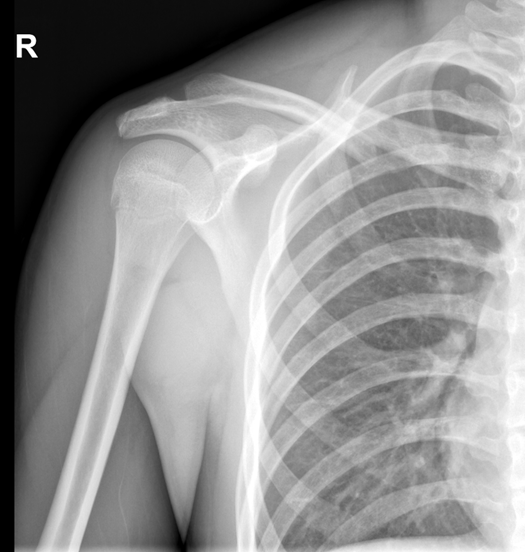

小陈在省级篮球选拔赛中意外摔倒,导致右侧锁骨中段骨折。X光片显示骨折断端错位明显,原本即将到来的体育单招考试面临取消。当地医院建议切开复位钢板内固定,但听说会留下8-10厘米疤痕,小陈和父母都十分犹豫。

经队友推荐,他们来到海医骨科手足外科门诊。俞张昊锐副主任医师仔细阅片并评估伤情后,提出了一个更优方案:“可以考虑弹性髓内针微创固定,只需要1厘米的小切口,术后恢复快,疤痕也隐蔽。”

(术前X线片)